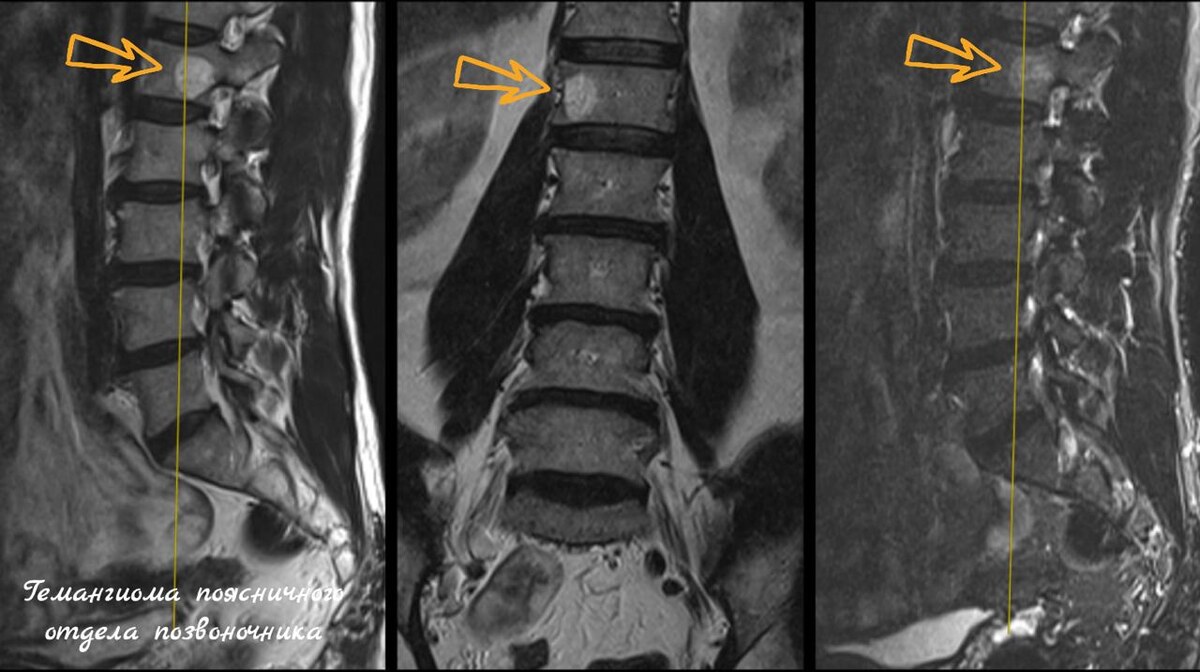

Локализованы гемангиомы чаще всего в грудном (до 80%, особенно Th6) или поясничном отделах позвоночника (15%, часто L2) , реже в шейном или крестцовом отделах.

гемангиома поясничного отдела